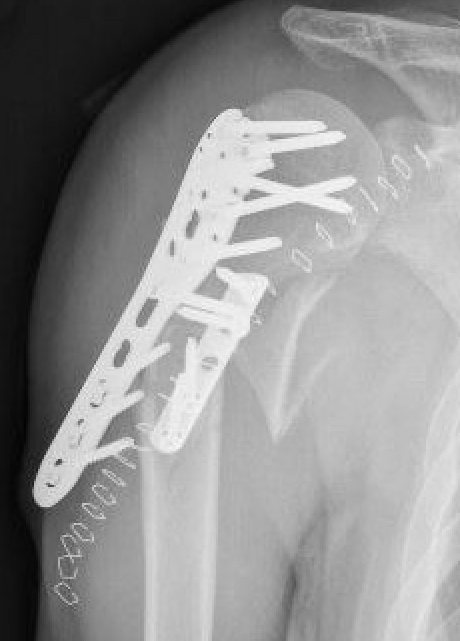

Plate

- narrow large fragment 4.5 mm DCP / long Philos proximal humeral plate

- minimum 6 cortices above and below

- can consider dual plate